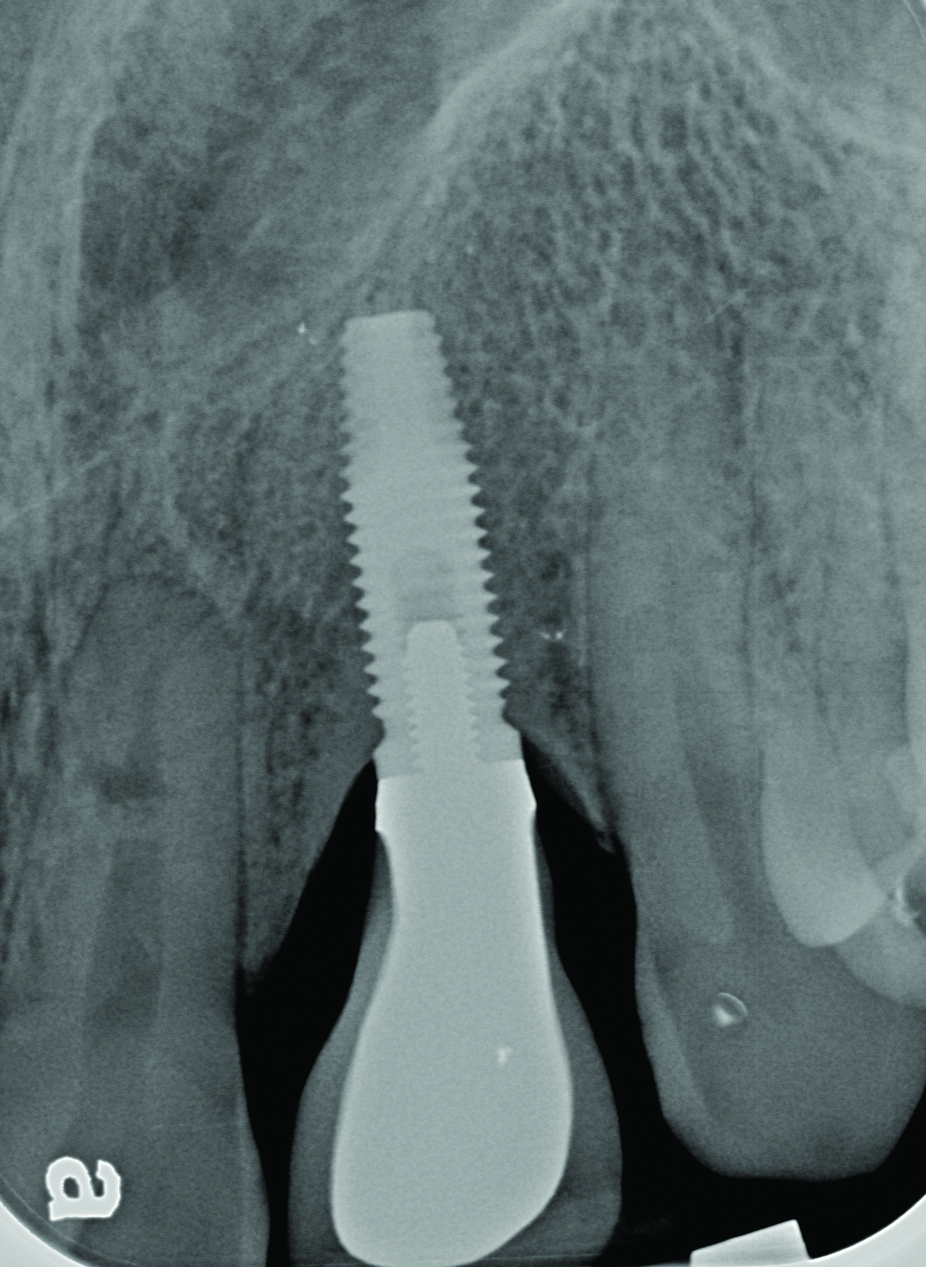

Radiograph of a mandibular left first molar implant in a 61-year-old man taken 2 years after the implant’s placement. No bone loss beyond physiologic remodeling has occurred.

Figure 5

Clinical view of this area suggests that peri-implant mucositis is present, as there is bleeding on light probing and inflammation of the tissue.

Figure 6

Four weeks following nonsurgical treatment, the area is healthy as probing depths are now shallow and bleeding is absent. Treatment involved scaling of the area, which removed all plaque and a slight amount of cement, and irrigation with an anti-inflammatory hydrogel.

Figure 7